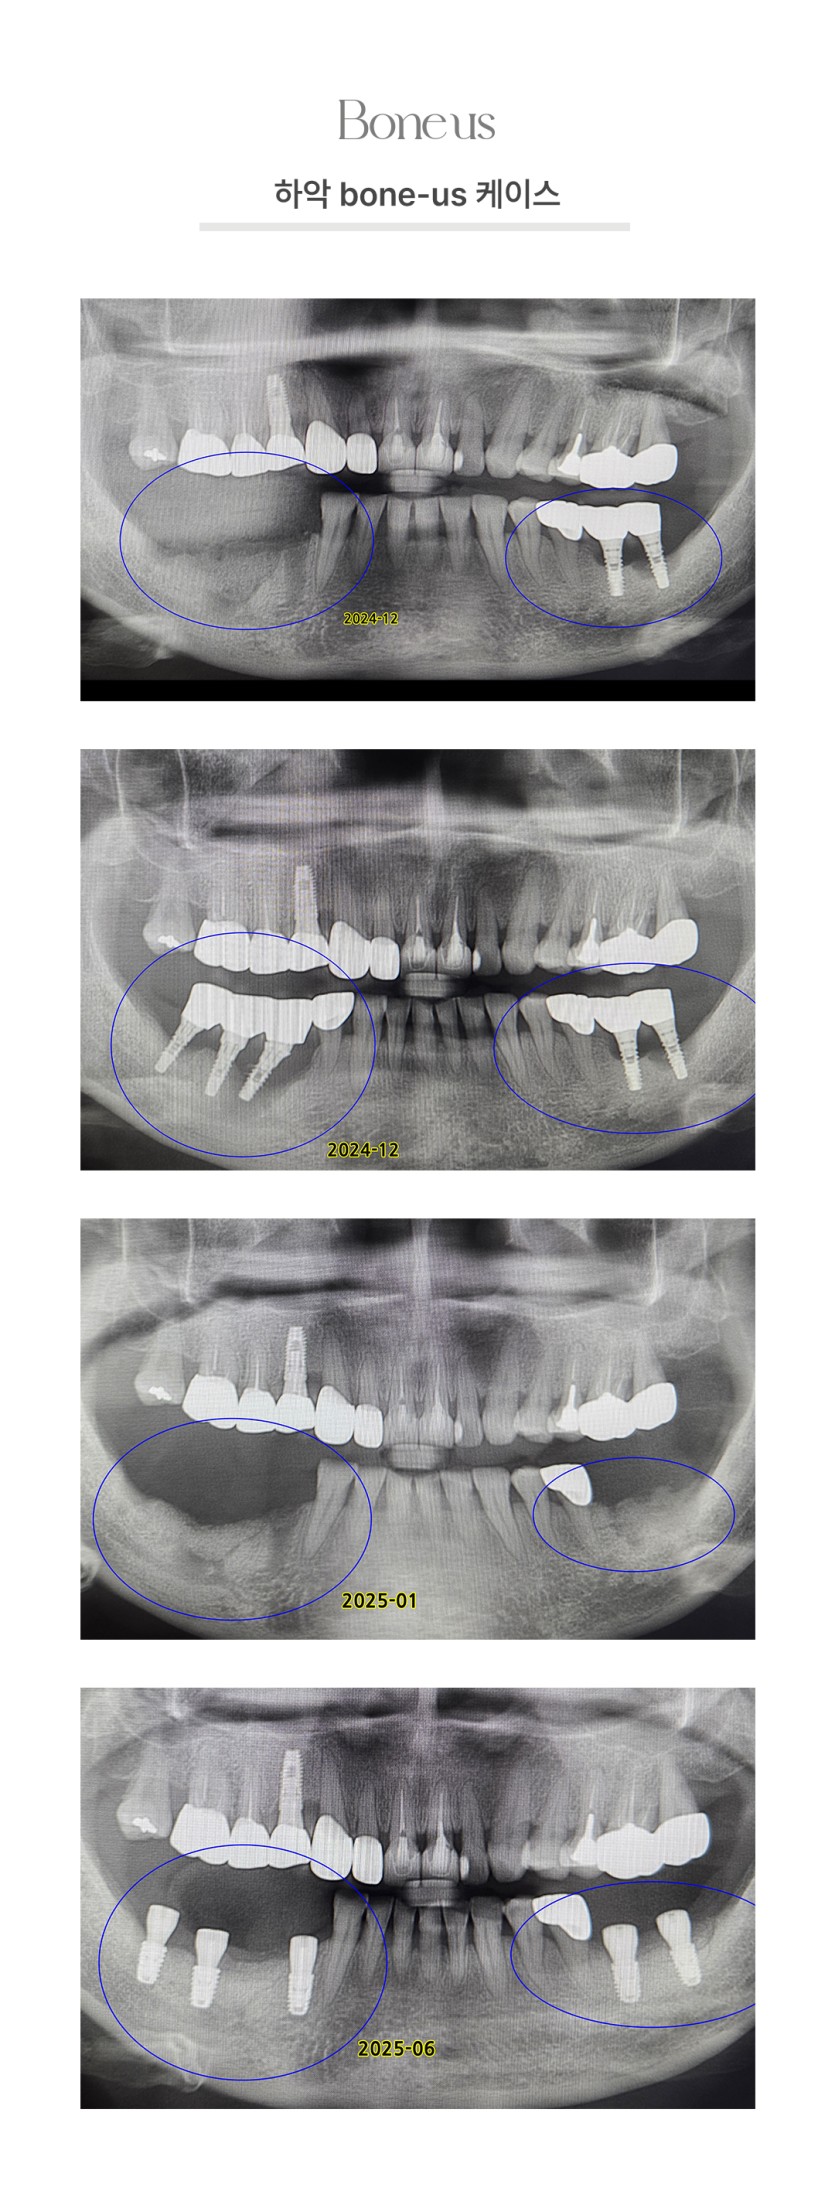

CLINICAL CASE

본어스 시술사례

하악 본어스 케이스 4